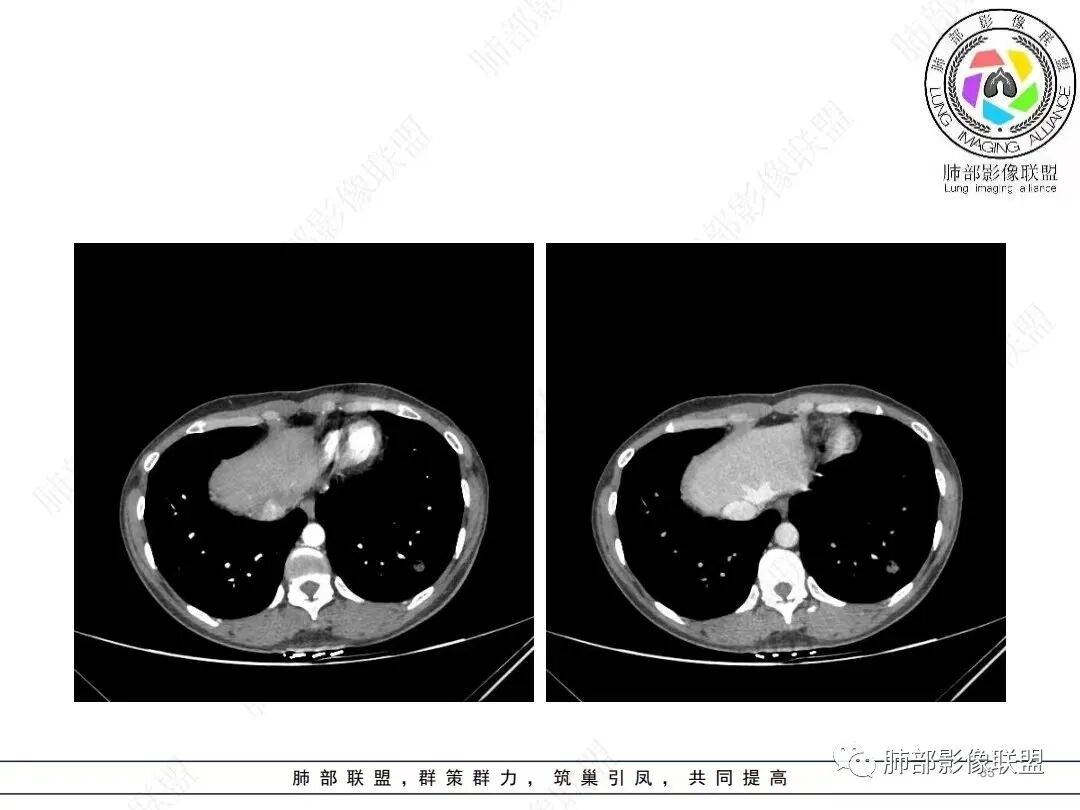

年轻女性,体检发现,左肺下叶亚实性结节,边缘有毛刺、分叶,磨玻璃晕,病灶内可见裂隙样空腔改变,纵隔窗显示实性小于肺窗,近端血管呈杵状增粗,考虑腺癌,鉴别炎性结节(隐球菌),转移性结节。

左下肺结节,局部边缘见u型凹陷及平直征,可见长毛刺,周围肺野可见斑点状播散灶,结节内可见低密度坏死,坏死边界清,坏死壁上可见结节堆彻,低强化,延迟强化呈环状,年轻患者,肿标阴性,综合分析首选炎性肉芽肿性病变,TB可能性大,其次鉴别腺癌

2、影像特点:左肺下叶类圆形结节影,周围可见多发细小毛刺,浅分叶,张力不高,未见胸膜牵拉。病灶内隐约见空泡影(未提供CT值),近端部分血管呈杵状增粗,可疑脐凹征。增强后实性部分有轻度强化。外围病灶,与支气管关系不明确。